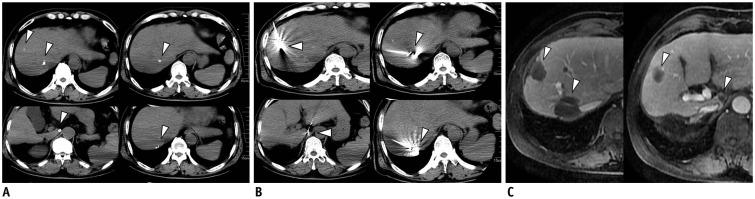

To evaluate the efficacy and prognostic factors associated with transcatheter arterial chemoembolization (TACE) combined with microwave ablation (MWA) versus TACE alone for a large solitary or multinodular hepatocellular carcinomas (HCCs).

This retrospective study involved 258 patients with a large solitary or multinodular HCCs (not more than 10 tumors) who underwent TACE + MWA (n = 92) or TACE alone (n = 166) between July 2011 and April 2015. Local tumor control, survival outcomes, and complications were compared between the two groups. Prognostic factors for time to progression (TTP) and overall survival (OS) were evaluated by univariate and multivariate analyses.

TACE + MWA appears to have more advantages compared to TACE in prolonging OS, with a satisfactory TTP, for inpatients with solitary large or multinodular HCCs. Treatment method, tumor size, and tumor number are significant prognostic factors for TTP and OS. Further randomized, multi-center, prospective trials are required to confirm the findings of this study.